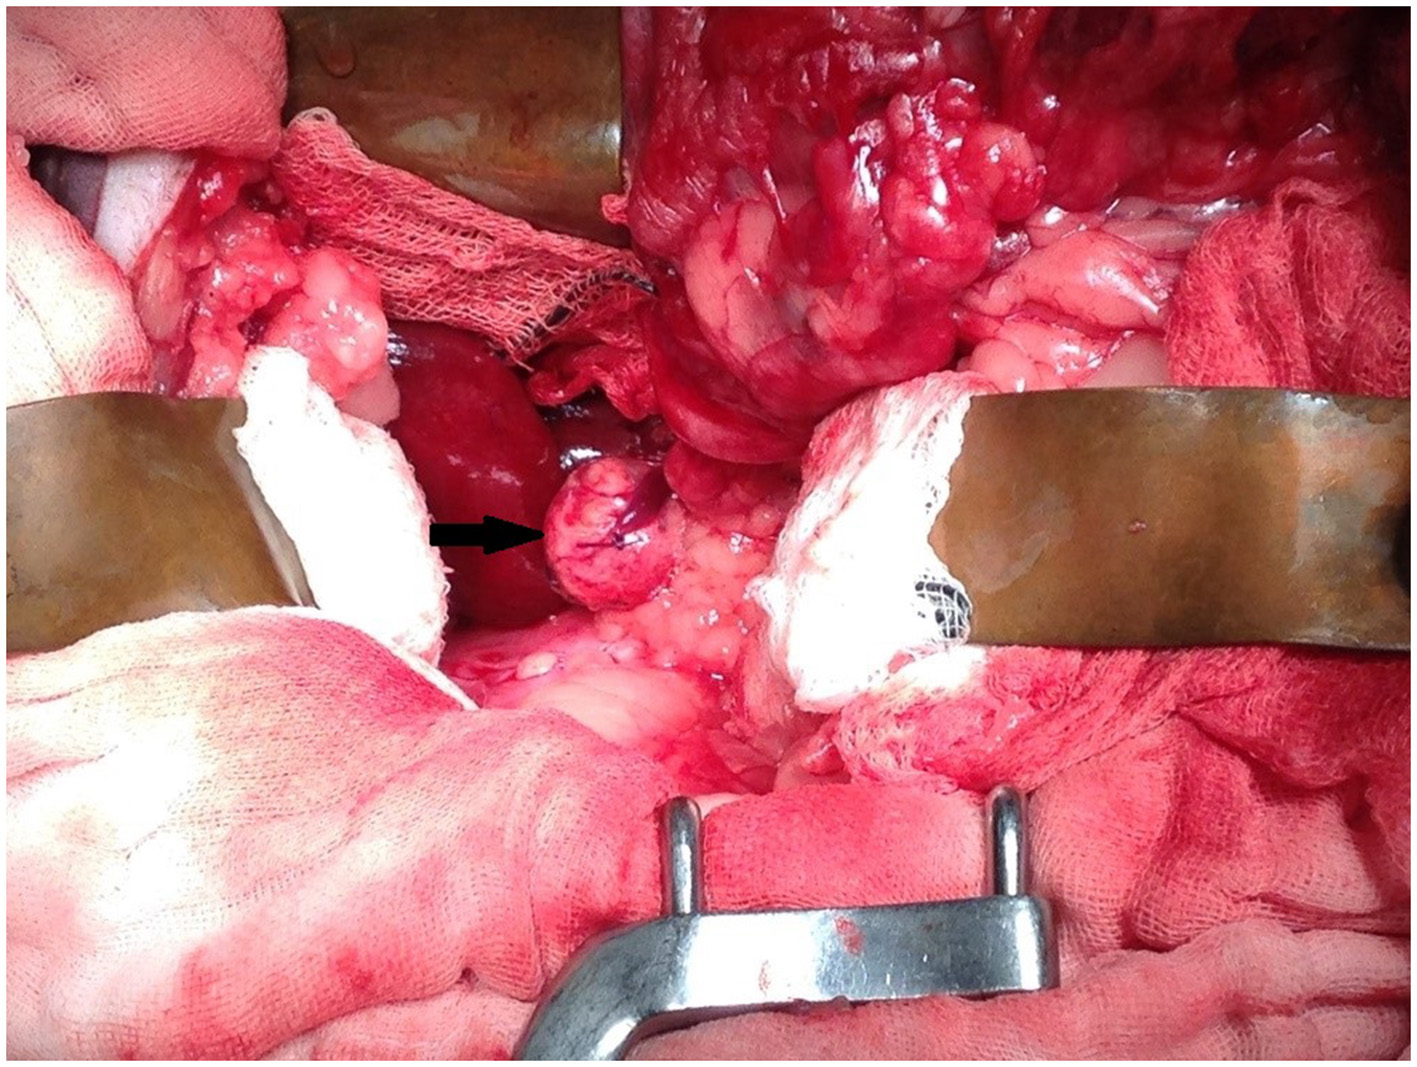

An 11-year-old female serval (Leptailurus serval) from Wellington Zoo was presented for a right adrenal mass, which had been progressively enlarging over the previous several months. The mass was initially found incidentally on abdominal ultrasound approximately 2 years previously while undergoing evaluation following a foreign body small intestinal obstruction (wood chip mulch). At initial diagnosis, the right adrenal gland was measured as 1.26 cm in comparison to the left adrenal gland, which measured 0.5 cm (Figure 1).

Figure 1. Ultrasound images of the right adrenal mass. (A) Initial ultrasound scan showing enlargement of the right adrenal gland (*). (B) A subsequent ultrasound scan approximately 11 months later showed progressive enlargement (calipers) of the right adrenal gland (*) and (C) in close association with the caudal vena cava (CVC, blue) but no evidence of invasion.

Successive abdominal ultrasounds indicated that the adrenal mass was expanding without evidence of invasion into the surrounding caudal vena cava or renal vasculature. The mass was encroaching on the right phrenicoabdominal vein but invasion into the vein could not be determined using ultrasound, and computed tomographic evaluation was recommended (Figure 1).